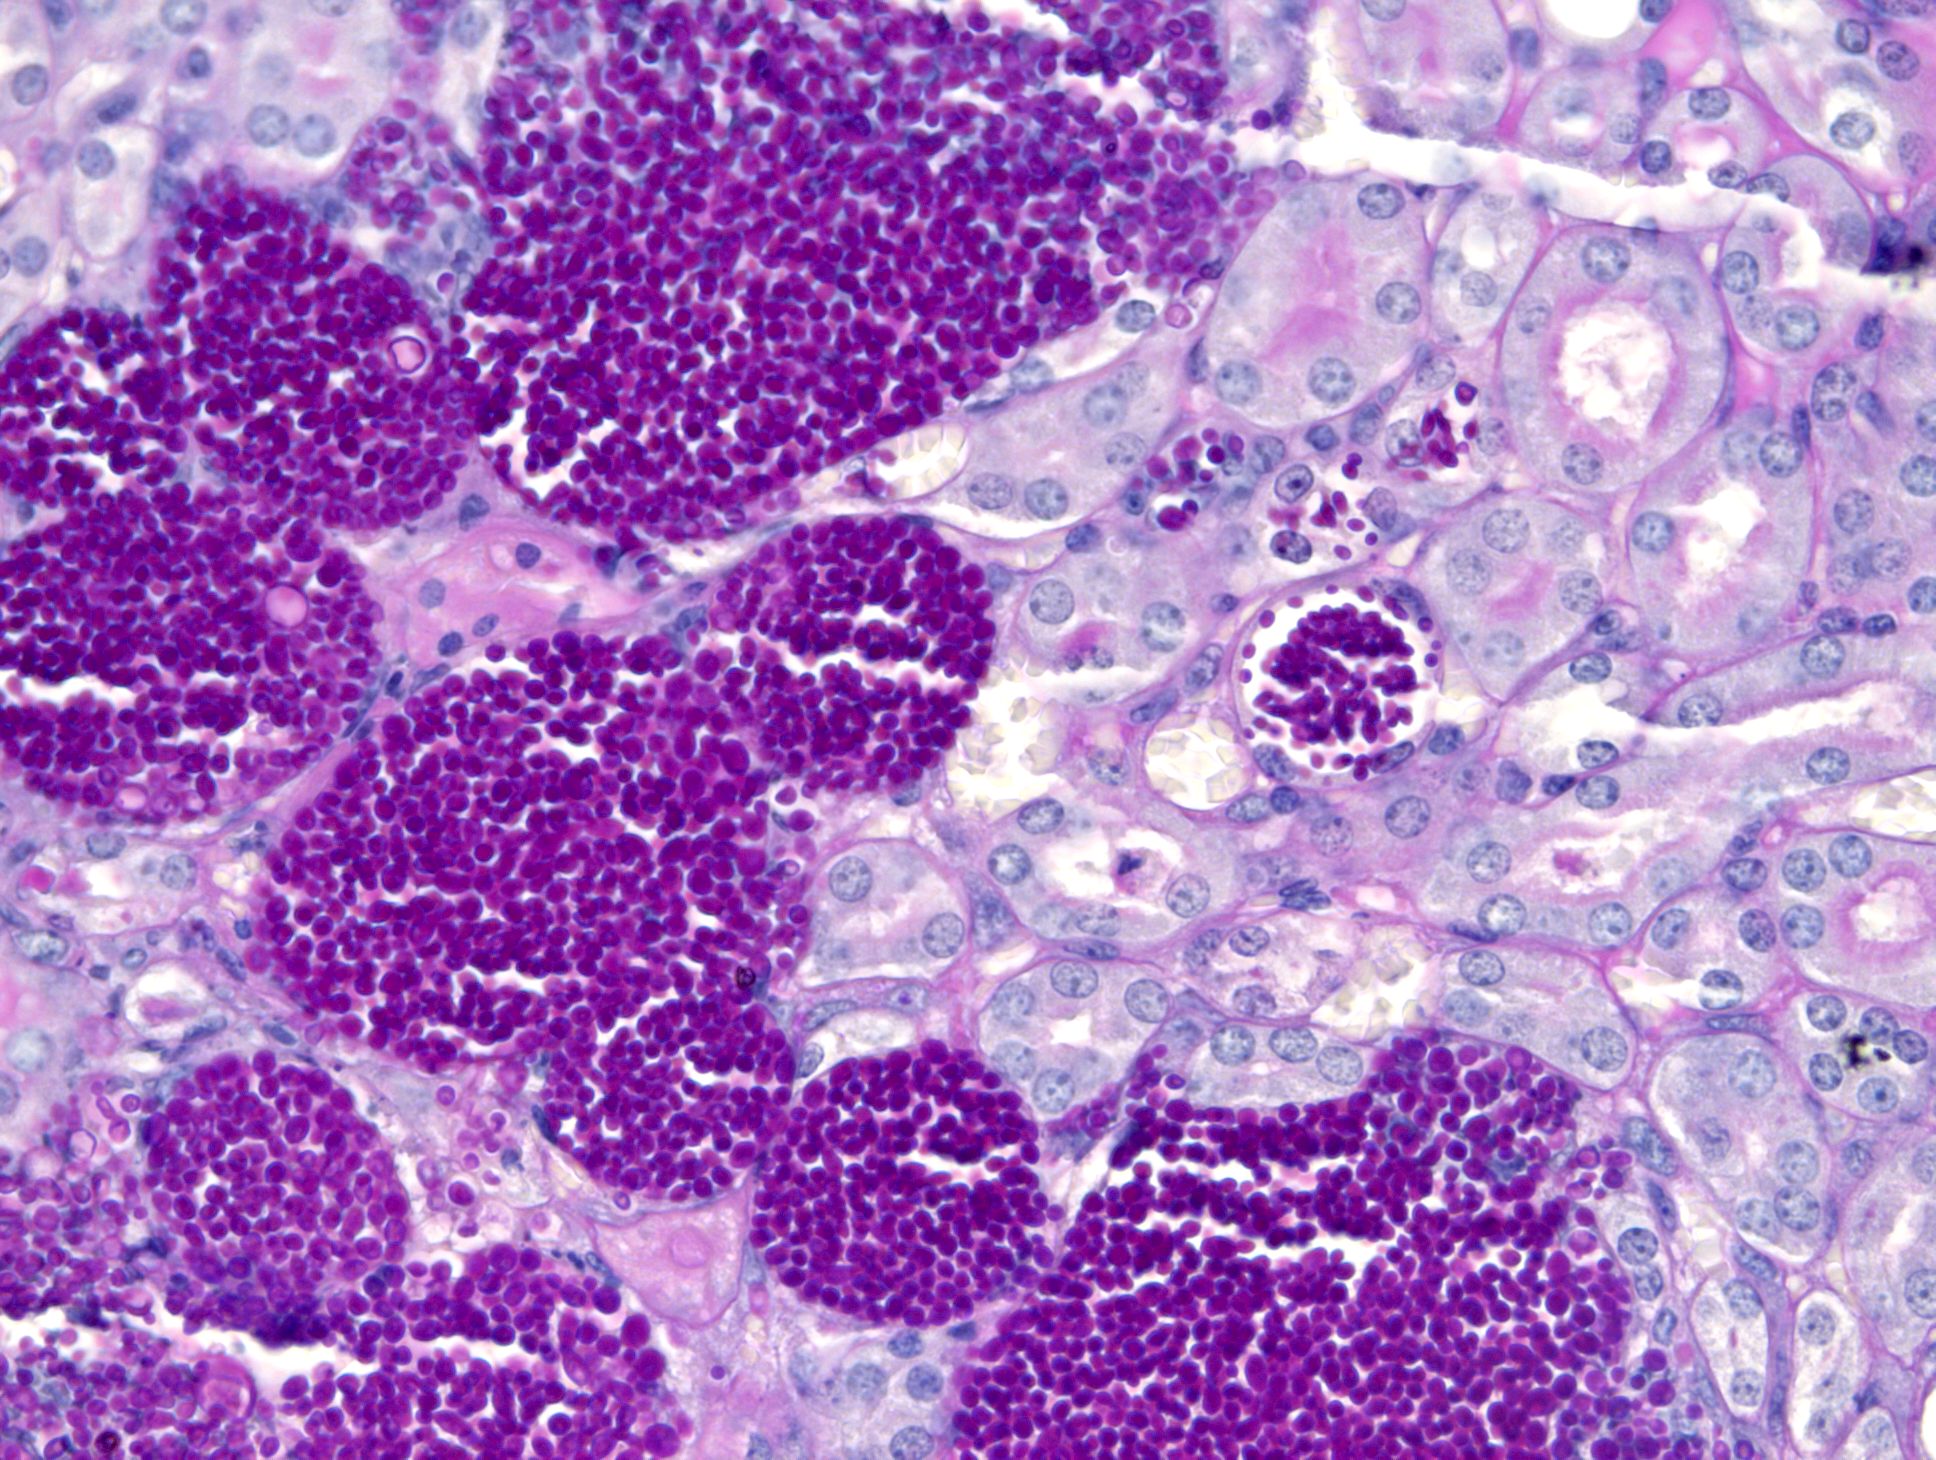

„Als wir uns das Gewebe der Tiere anschauten, fanden wir eine hundertfach höhere Pilzbelastung der Organe“, so Christine Dunker. Sie ist Doktorandin in Jacobsens Team und Erstautorin der Studie. „Der Pilz konnte sich in den Organen blitzschnell vermehren. Durch diese hohe Menge an Pilzzellen beispielsweise im Nierengewebe entstand ein enormer Druck, der die Organe schließlich erheblich schädigte.“ Auch die Reaktion des Immunsystems hat eine Auswirkung auf den schweren Krankheitsverlauf: „Die Makrophagen, also unsere Fresszellen, erkannten den Pilz zwar zu Beginn der Infektion. Jedoch schlug das Immunsystem erst in einem späteren Stadium Alarm und veranlasste die Bildung einer Vielzahl von weißen Blutkörperchen, sogenannte neutrophile Granulozyten“, ergänzt Dunker. „Beim Versuch die Eindringlinge abzutöten, lösten die Immunzellen starke Entzündungsreaktionen aus und schädigten das Gewebe zusätzlich. Dieser Kollateralschaden ist aufgrund der Pilzmenge größer als beim Wildtyp.“